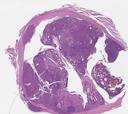

病理切片